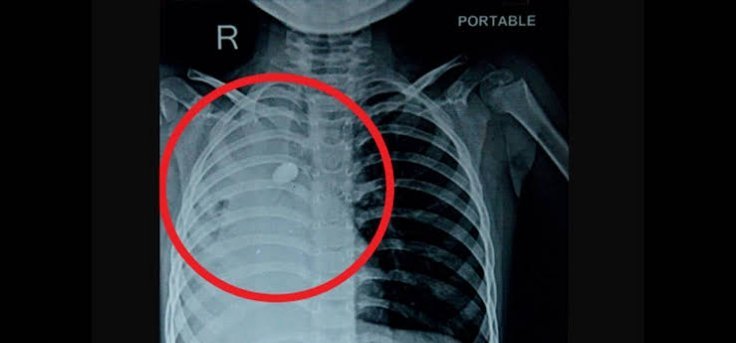

इस बाबत जानकारी देते हुए पल्मोनरी मेडिसिन विभाग के एडिशनल प्रोफेसर डॉ. मयंक मिश्रा ने बताया कि टीम वर्क से संपन्न की गई इस प्रक्रिया से चिकित्सकों की टीम, बच्चे की श्वास नली में फंसी गिट्टी को बाहर निकालने में सफल रही। डॉ. मयंक ने बताया कि निकाली गई गिट्टी का साईज 1.5×1 सेमी. था। 16 जुलाई को ब्रोंकोस्कॉपी की प्रक्रिया संपन्न करने के बाद स्वस्थ होने पर बच्चे को पिछले सप्ताह एम्स से डिस्चार्ज कर दिया गया।